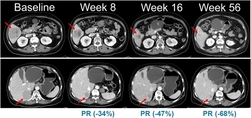

한미약품이 국내 최초로 악성 피부암인 흑색종 치료를 위한 경구용 표적 항암신약 ‘벨바라페닙’의 국내 임상 2상에서 환자 투약을 시작했다. 한미사이언스 핵심 사업회사 한미약품은 지난 12일 국내 대학병원에서 NRAS 돌연변이를 보유한 국소 진행성 또는 전이성 흑색종 환자를 대상으로 ‘벨바라페닙(Belvarafenib)’을 평가하는 2상 임상시험에 참여하는 첫 번째 환자를 등록하고 첫 투약을 완료했다고 19일 밝혔다. 한미약품이 지난 1월 식품의약품안전처로부터 벨바라페닙의 국내 임상 2상 시험계획서(IND)를 승인받은 이후 환자 투약까지 불과 한 달여 만에 신속하게 이뤄졌다는 점에서 주목된다. 이번 임상 2상은 총 45명의 환자를 대상으로 표적 항암신약 벨바라페닙과 MEK 억제제인 코비메티닙(Cobimetinib) 병용요법의 유효성과 안전성을 평가하기 위한 다기관, 단일군 시험으로 진행된다. 흑색종은 치료 옵션이 제한적이고 재발 위험이 높은 난치성 암으로, 현재 치료제 대부분이 해외 제약사를 통해 공급되고 있다. 특히 NRAS 돌연변이 흑색종은 예후가 불량하고 국내외 허가된 표준 치료제가 없는 의료적 미충족 수요가 높은 영역으로, 현재 의료 현장에서는 벨바라페닙